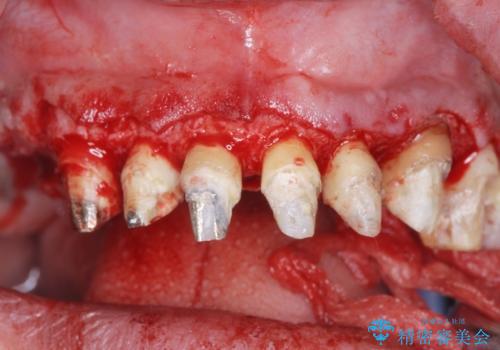

- 「セラミック治療を他院で受けたが、それ以来歯ぐきが腫れ違和感がある、改善してほしい。」と歯ぐきの状態改善を希望され来院されました。

歯周組織検査を行うと歯ぐきからは容易に出血し、X線検査より歯とセラミッククラウンの適合が悪い(ピッタリと合っていない)状態が示唆され、歯ぐきの炎症を惹起している状態でした。

セラミッククラウンを除去し仮歯を装着し、歯周外科手術を行い歯ぐきの状態を改善したのち、適合の良いセラミッククラウンを再作製をする治療計画としました。